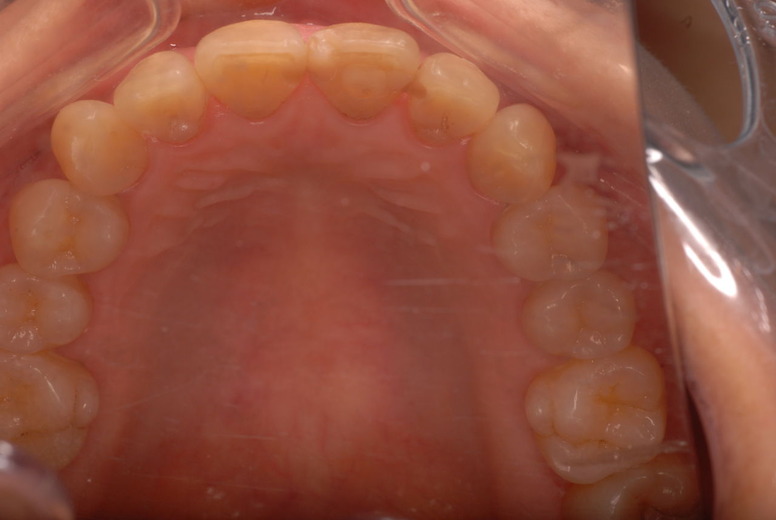

殆ど出っ張りがない上顎の部分です。

歯周病になっていましたが、少し色が黄色くなっているだけで比較的綺麗な歯の状態です。

平成9年来院神経を取り、同時に歯周病の話をしてそのまま来なくなっていたかたですが、たまたま一部欠けてきました。それで来院。